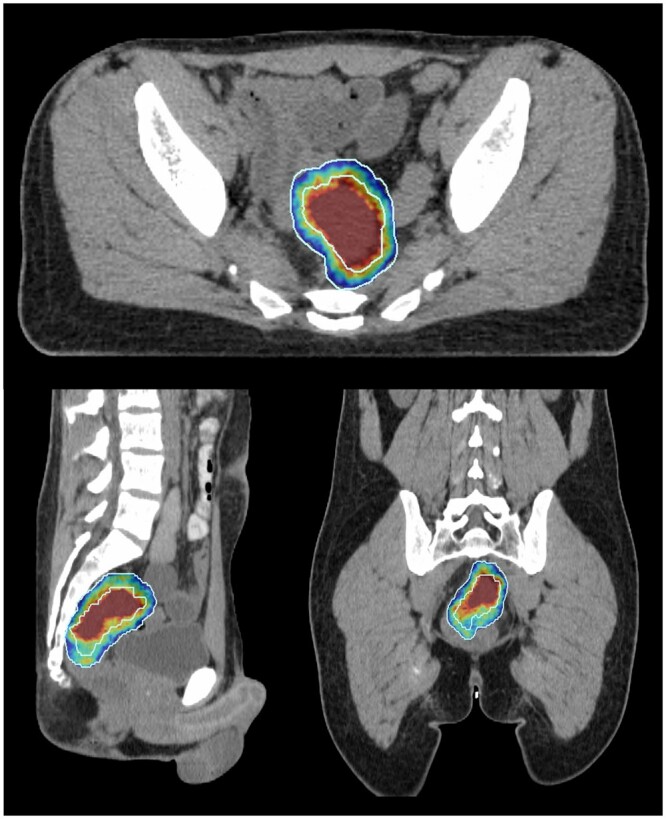

Methods: Ten patients previously treated with curative-intent standard long-course radiotherapy (50 Gy/25#) were re-planned. Boost target volumes (BTVs) were delineated semi-automatically using 40th centile intra-tumoural apparent diffusion coefficient value with expansions (anteroposterior 11 mm, transverse 7 mm, craniocaudal 13 mm). Biased-dosed combined plans consisted of a single-fraction volumetric modulated arc therapy flattening-filter-free (VMAT-FFF) boost (phase 1) of 5, 7, or 10 Gy before long-course VMAT (phase 2). Phase 1 plans were assessed with reference to stereotactic conformality and deliverability measures. Combined plans were evaluated with reference to standard long-course therapy dose constraints.

Results: Phase 1 BTV dose targets at 5/7/10 Gy were met in all instances. Conformality constraints were met with only 1 minor violation at 5 and 7 Gy. All phase 1 and combined phase 1 + 2 plans passed patient-specific quality assurance. Combined phase 1 + 2 plans generally met organ-at-risk dose constraints. Exceptions included high-dose spillage to bladder and large bowel, predominantly in cases where previously administered, clinically acceptable non-boosted plans also could not meet constraints.

Abstract Image